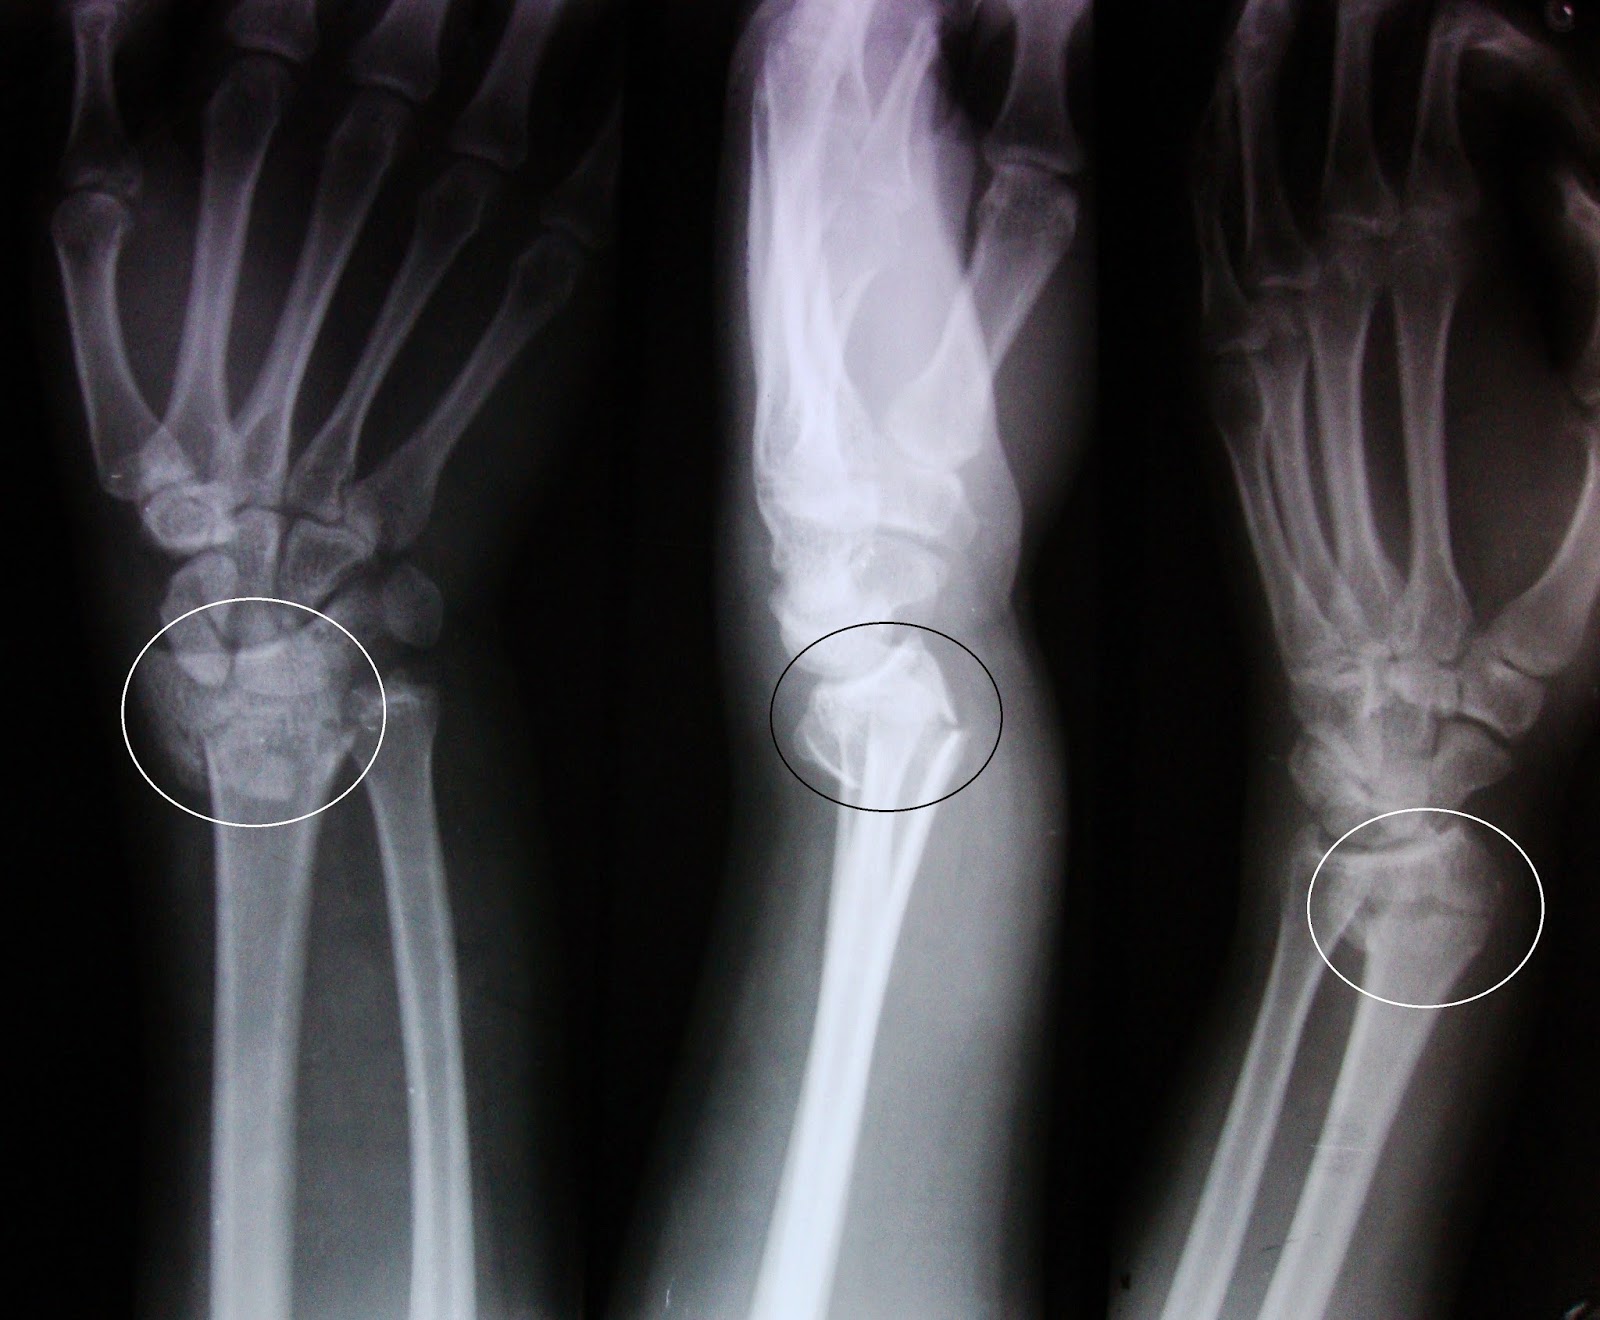

Το κάταγμα Colles αποτελεί ένα από τα πιο γνωστά κατάγματα του χεριού. Πρόκειται για εγκάρσιο κάταγμα της κερκίδας, περίπου 20-35 εκατοστά από την πηχεοκαρπική άρθρωση. Το κάταγμα του κάτω πέρατος της κερκίδας περιγράφηκε πρώτη φορά το 1814 από τον Abraham Colles, προς τιμή του οποίου πλέον αναφέρεται ως «Κάταγμα Colles». Ο Abraham Colles (1773 – 1843) περιέγραψε το κάταγμα αυτό ως εξής: Ήταν κοντά στην άρθρωση του καρπού, σε απόσταση έως 2.5cm από αυτή. Συνοδευόταν από κάταγμα της στυλοειδούς απόφυσης της ωλένης και εμφάνιζε ραχιαία μετατόπιση του περιφερικού τμήματος.

Χαρακτηρίζεται από ραχιαία και κερκιδική παρεκτόπιση του περιφερικού τμήματος με ταυτόχρονη κλίση της αρθρικής επιφάνειας της κερκίδας προς τα άνω (ραχιαία), ενώ φυσιολογικά έχει κλίση ελαφρά προς τα κάτω (παλαμιαία).Ο ασθενής παρουσιάζει πόνο, τοπικό οίδημα, αδυναμία στις κινήσεις της πηχεοκαρπικής. Το κάταγμα αυτό, προκαλεί χαρακτηριστική παραμόρφωση του χεριού που παίρνει το σχήμα πιρουνιού.

Ακτινολογικά, παρουσιάζεται η παραμόρφωση που προαναφέρθηκε, ενώ σε αρκετές περιπτώσεις συνυπάρχει κάταγμα της στυλοειδούς απόφυσης της ωλένης.